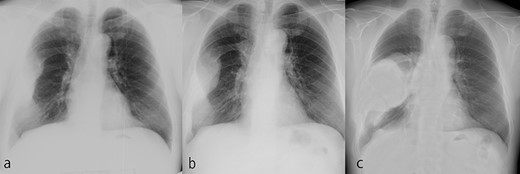

The tumor grew over the course of 22 years after reaching adulthood. (a) Chest X-ray at 50 years old. (b) Chest X-ray at 58 years old. (c) Chest X-ray at 72 years old.

A 72-year-old man was referred to our department with a suspected tumor in the right rib. An abnormal shadow in the right chest was found during screening at 50 years of age. The patient was later followed up intermittently by a general physician (Fig. 1a and b). At 72 years of age, he was referred to our department because of a suspected malignant tumor. There were neither subjective symptoms nor abnormal physical findings. A blood test revealed an elevated level for alkaline phosphatase alone at 706 U/L. A pulmonary function test showed a percent vital capacity (%VC) of 78.8%, indicating a mild restrictive impairment. Plain radiography showed a radiopaque tumor measuring 12 × 9 × 18 cm that was connected to the seventh rib in the right thoracic cavity (Fig. 1c). When compared to previous images, the tumor had gradually grown over the preceding 22 years. Computed tomography (CT) showed an extra-osseous tumor-like lesion with calcification, cortical destruction of the right seventh rib and a similar small lesion in the right ninth rib (Fig. 2). Moreover, lesions were also detected in the ninth thoracic vertebral body. Magnetic resonance imaging (MRI) revealed a lower signal intensity inside the lesion compared to the muscle on T1-weighted images and a mixture of low and high intensity on T2-weighted images, while enhancement was observed in the lower intensity area on T2-weighted images (Fig. 3a and b). Bone scintigraphy and positron emission tomography/computed tomography (PET/CT) revealed an increased uptake in the right seventh and ninth ribs and ninth vertebral body, and the right seventh rib showed a high standard uptake value at 7.67 on PET/CT (Fig. 4a and b).